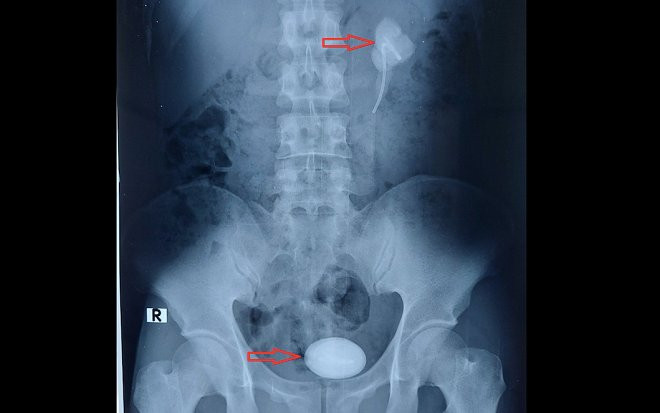

Hình ảnh sỏi vùng bể thận - niệu quản phía trên và sỏi bàng quang có kích thước như quả trứng ngỗng. (Ảnh: Thanh Niên)

Tiến hành siêu âm và chụp cắt lớp vi tính hệ niệu, các bác sĩ tại Bệnh viện đa khoa Trung ương Cần Thơ ghi nhận: Thận trái bệnh nhân ứ nước độ 2, sỏi vùng bể thận - niệu quản bên trái, kích thước khoảng 30 x 58 mm, sỏi bàng quang kích thước 90 x 58 mm, có một đoạn ống thông niệu quản JJ trong cả 2 viên sỏi.